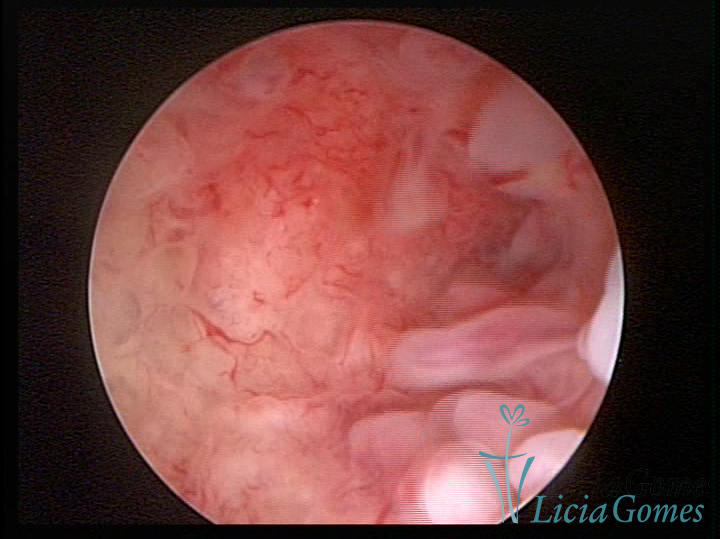

Este pode apresentar uma gama variável de aspectos macroscópicos, com aspecto pseudopolipoide; lembrando tecido cerebroide ou com reação deciduoide;a vascularização superficial é mais evidente e com vasos em formatos de saca-rolha ou espirais visualizando também a vascularização com atípias, com aumento do calibre dos vasos superficiais, pode ser encontrado também tecido em necrose, poderá haver um pequenos dendritos (papilomatoso).